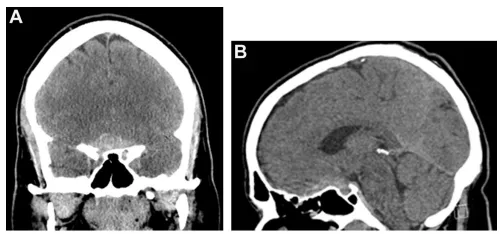

头颅CT检查显示鞍上区存在高密度占位性病变,该病灶沿蝶骨平台向前延伸(图1A、1B)。

图1.(A、B)冠状位及矢状位平扫CT显示鞍上区高密度占位性病变,沿蝶骨平台向前延伸。

随后的CT血管造影检查排除了血管性病变。进一步MRI检查发现一个4厘米大小的非强化斑块样肿瘤,紧密贴附视交叉,并压迫垂体柄及垂体(图1C、1D)。

(C、D)冠状位及矢状位磁共振成像(MRI)提示视交叉旁非强化性、轴外斑块状4cm占位,压迫垂体柄及垂体腺。

令人惊讶的是,4周后复查MRI显示原蝶骨平台及鞍上占位病变接近完全消失(图1E、F)。患者认为病情已缓解,未继续规律随访。

(E、F)4周后随访MRI冠状位及矢状位扫描显示原蝶骨平台及鞍上占位病变接近完全消失。